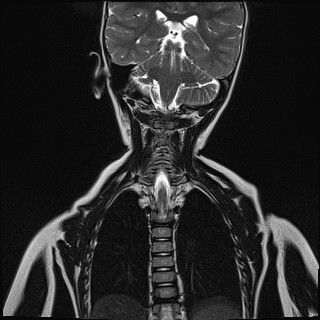

A lo largo de casi 4 meses de estudio se realizan radiografía de rodilla y de columna cervical (normales); analítica sanguínea (ANA positivo (1/320), factor reumatoide y resto de anticuerpos negativos); prueba de Mantoux (negativo); artrocentesis de rodilla (líquido de características inflamatorias) y resonancia magnética nuclear (RNM) cervical con hallazgo de sinovitis atlantoaxoidea (Fig. 1). Tras el diagnóstico de AIJ oligoarticular ANA positivo, se lleva a cabo un estudio por Oftalmología, sin objetivar uveítis en controles posteriores.

| Figura 1. RNM donde se aprecia líquido rodeando masas laterales del atlas, en articulaciones atloaxoideas y aumento de partes blandas rodeando odontoides y entre arco anterior de C1 y membrana tectorial, que tras introducción de contraste intravenoso muestra captación, indicativo de sinovitis activa atlantoaxoidea |